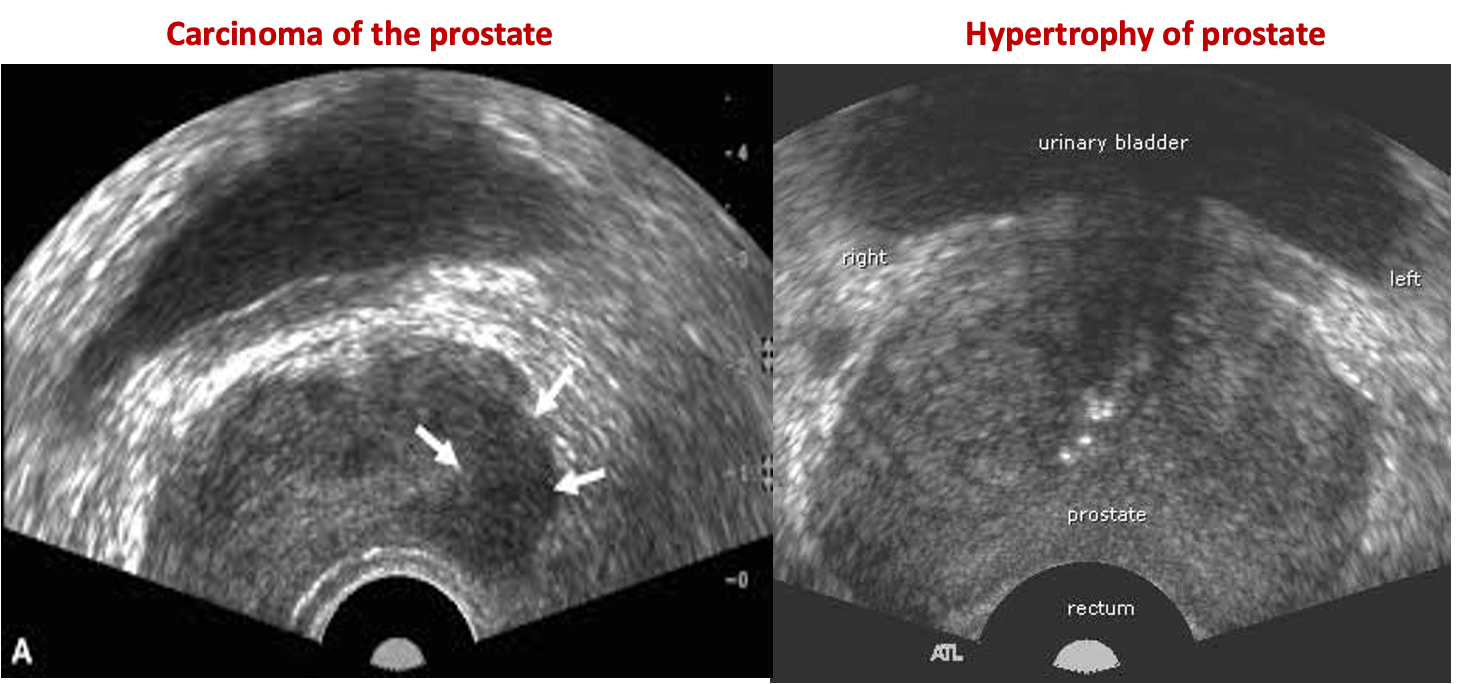

- Transrectal ultrasonography is an accurate way to measure prostate volume.

- Transrectal biopsy is usually done with ultrasound guidance and is usually only indicated if there is suspicion of prostate cancer.

Transrectal ultrasound (TRUS):

TRUS is not required for the initial evaluation of BPH.

Indications

- Suspected prostate cancer to guide biopsy

Transrectal ultrasound images of prostate